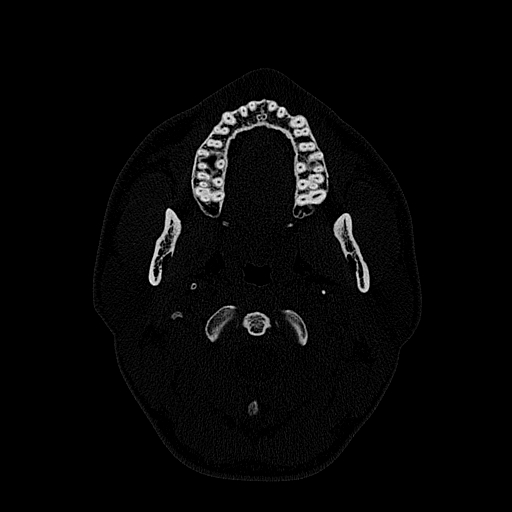

Мультиспиральная дентальная компьютерная томография (МДКТ или, как ее еще называют, КТ зубов) – это современный высокоточный метод лучевой диагностики, с помощью которого получают объемные цифровые изображения всей зубочелюстной системы. В основе метода лежит применение рентгеновского излучения и последующая цифровая обработка полученных данных специальными компьютерными программами.

Мультиспиральный томограф выполняет послойное сканирование области верхней и нижней челюстей с помощью рентгеновских лучей, а затем, используя компьютерную обработку данных, создает 3D-модели исследуемой зоны. Современные модели томографов проводят круговое сканирование по спирали, делая срезовые снимки на расстоянии 0,5 мм друг от друга. Затем на основе этих данных реконструируются детальные изображения челюстно-лицевой области в трехмерном формате.

Исследование занимает всего пару минут. Данные, полученные при сканировании, проходят цифровую обработку и выводятся на монитор компьютера в виде 3D-изображений. Врач-рентгенолог внимательно анализирует данные и выдает заключение.

Высокая информативность исследования за счет детальных снимков и наглядных пространственных 3D-реконструкций позволяет увидеть то, что недоступно для визуального осмотра и обычного рентгеновского обследования.

Дентальная КТ показывает:

- Особенности костных структур, толщину и плотность костной ткани (например, при планировании имплантации данные ДКТ позволяют решить, необходимо наращивать костную ткань или нет).

- Воспалительные процессы зубочелюстного аппарата и их осложнения.

- Строение корней зубов наличие кист, гранулем, состояние пломбировочного материала.

- Патологии прикуса, дистопию зубов (неправильное положение отдельных единиц).

- Непрорезавшиеся (ретинированные) зубы.